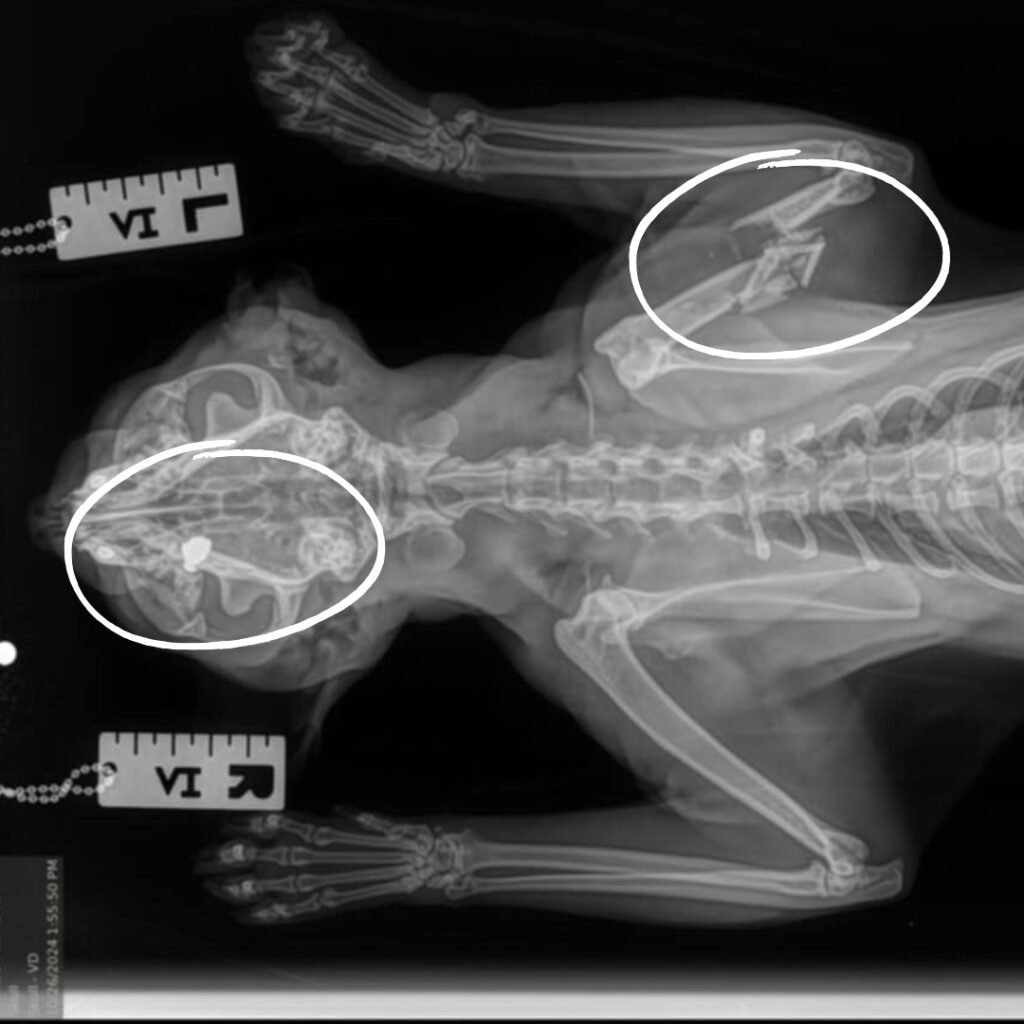

Poe arrived at KHS last week with extreme injuries caused by a gunshot. We jumped into action upon his arrival by providing him with pain medication and antibiotics to keep him comfortable as we assessed his wounds. Our hearts broke when x-rays revealed a severe break to Poe’s front right leg along with bullet and bone fragments littering his little body. The trauma he must have endured is unthinkable.

Poe, a two-year-old black cat, arrived at our Sam Swope Pet Treatment and Lifesaving Center this week with heartbreaking injuries caused by a gunshot. X-rays revealed this poor kitty’s front right leg was severely wounded, and his humerus bone was shattered by a bullet. Shrapnel litters his body and is even lodged behind his left eye. We can’t imagine the cruelty this sweet cat endured.

Our team is providing Poe with pain medication and antibiotics to keep him comfortable and infection-free while he heals. We’ve splinted his leg and hope his injuries will heal with time and rest. However, Poe will need to remain under observation so we can determine if an amputation surgery is needed. For now, we are grateful that this loving cat came to KHS where he is receiving the tender loving care he desperately needs and deserves. Please to support lifesaving, emergency medical care for vulnerable animals like Poe. Together, we can stand behind every broken, abused and neglected animal who comes through our doors.